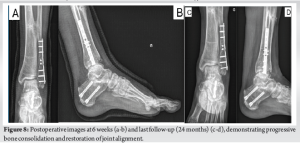

The causative fracture was a left tibia-fibula fracture in early childhood due to a road traffic accident, treated conservatively with casting. The lateral malleolar fracture was insufficiently reduced, resulting in significant fibular shortening. The 57-year-old patient presented with chronic lateral-dorsal pain in the left ankle, clinically accompanied by hindfoot valgus deformity and limited mobility with a submalleolar and anterior ankle impingement. The X-rays show bone remodeling and tibiofibular arthrodesis at the distal third (Fig. 1). Additional imaging included scintigraphy showing progressive tibio-talar osteoarthritis and early-stage Lisfranc joint osteoarthritis (Fig. 2). MRI and CT confirmed post-traumatic fibular shortening, consequent hindfoot valgus, and partially misaligned tibio-talar osteoarthritis in the lateral compartment (Figs. 3-5). Surgical management was indicated for the angular malunion, involving medializing calcaneal osteotomy and fibular lengthening osteotomy on the left ankle. Preoperative planning included standing anteroposterior (AP) and lateral radiographs of the ankle and hindfoot, as well as hindfoot alignment views (Saltzman view) to assess coronal malalignment. Full-length standing radiographs of both lower limbs were obtained to evaluate the mechanical axis. CT scan was used to precisely measure the degree of fibular shortening and tibiofibular joint fusion. MRI allowed for soft tissue and cartilage evaluation, particularly at the tibio-talar joint. Fibular shortening was assessed by comparing the level of the lateral malleolus to the plafond tibial and to the medial malleolus on the contralateral, uninjured side. Correction planning aimed to restore the fibular length to reestablish the normal relationship, targeting the lateral malleolus tip approximately 5–7 mm distal to the talar dome on the mortise view, which corresponds to the physiological fibular station. Angular correction involved planning for a 10° medial translation at the calcaneus level to correct the hindfoot valgus, based on hindfoot alignment measurements. Five weeks later, arthroscopy was performed for osteophyte removal as a second stage. The surgical procedure involved a Z-lengthening osteotomy of the , achieving approximately 9 mm of lengthening, fixed with two compression screws and a neutralization plate, supplemented by a corticocancellous graft harvested from the left anterior iliac crest (Fig. 6). The medializing calcaneal osteotomy required a medial displacement of the large tuberosity by 10 . The 10-mm medial shift was determined based on hindfoot alignment analysis, correcting approximately 1 mm/degree of valgus. This was achieved through lateral cortical osteotomy with the saw and medial completion with an osteotome, then fixed with two partially threaded titanium 7.0 compression screws (FixosR, Stryker, Mahwah, NJ 07430 USA) (Fig. 7). The surgery was performed under scopic guidance. Postoperatively, the non-weight-bearing period extended to 5 weeks, followed by an arthroscopy for osteophyte removal performed after the cast immobilization period. Physiotherapy was initiated 2 weeks later, following suture removal, with full weight-bearing allowed using a stabilizing ankle brace. No intra-operative or early postoperative complications were reported. Postoperative radiographs obtained at 6 weeks and at the final follow-up (24 weeks) illustrate satisfactory healing and a favorable clinical outcome (Fig. 8).